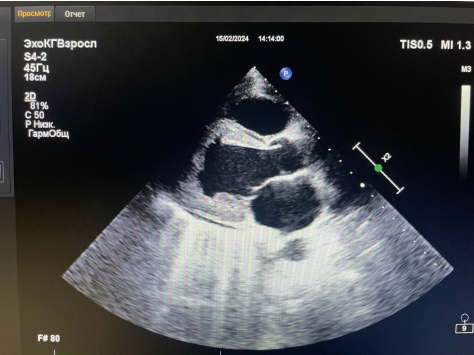

Рис. 2. Фото трансторакальной ЭхоКГ от 15.02.2024. Парастернальная позиция по длинной оси ЛЖ.

Поступление в гематологическое отделение городской больницы (13.02-15.02.2024). Стернальная пункция: в миелограмме бласты 0,6%, эозинофилы 45%. Эозинофильный лейкоз исключен. ЭхоКГ (15.02.2024): лоцируется разрастание эндокарда, выстилающее верхушку ЛЖ с переходом на передне-боковую стенку размерами 36×36 мм с поражением задней створки МК, разрастание эндокарда в полости ПЖ у верхушки — ЭЛ? Гипокинез верхушки с незначительным снижением ФВ ЛЖ 53%. Недостаточность МК III степени (объем ЛП 38 мл), трикуспидального клапана II степени. Признаки умеренной легочной гипертензии, СДЛА 38 мм рт.ст. Пограничный гидроперикард (рис. 1, 2) |